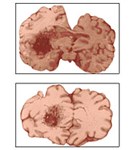

При сочетании трех и более неблагоприятных факторов предрасположение к инсульту увеличивается. По характеру изменений в головном мозге инсульты разделяют на две большие группы: геморрагические и ишемические.

К геморрагическому относят кровоизлияние в вещество мозга либо под его оболочки (субарахноидальное кровоизлияние). Кровоизлияния обычно возникают в результате разрыва мозгового сосуда, обусловленного высоким артериальным давлением.

Причиной ишемического инсульта, напротив является недостаточный приток крови к тем или иным участкам мозга вследствие сужения или полной закупорки питающих их сосудов. Иногда встречается комбинация этих двух видов инсультов.